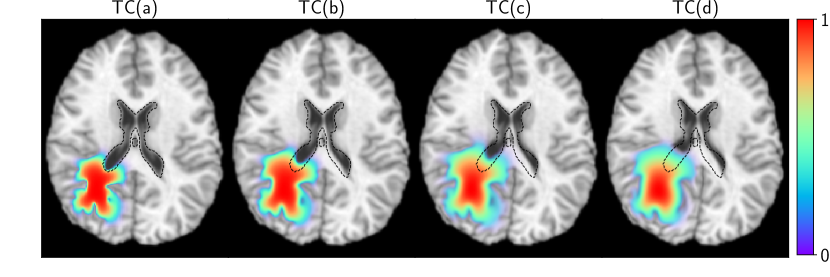

(Q1) Known m0subscript𝑚0\boldsymbol{m}_{0}, known p𝑝\boldsymbol{p}: In this experiment, we generate data by growing synthetic tumors resembling clinical observations in a healthy atlas using different ground truth parameter combinations. The test-cases are aimed at simulating similar tumor volumes, but with varying amount of mass effect. We consider the following variations for our parameter configurations:

(i) TC(a): no mass effect γ=0superscript𝛾0\gamma^{\star}=0 ρ=12superscript𝜌12\rho^{\star}=12 κ=0.025superscript𝜅0.025\kappa^{\star}=0.025

(ii) TC(b): mild mass effect γ=0.4superscript𝛾0.4\gamma^{\star}=0.4 ρ=12superscript𝜌12\rho^{\star}=12 κ=0.025superscript𝜅0.025\kappa^{\star}=0.025

(iii) TC(c): moderate mass effect γ=0.8superscript𝛾0.8\gamma^{\star}=0.8 ρ=10superscript𝜌10\rho^{\star}=10 κ=0.05superscript𝜅0.05\kappa^{\star}=0.05

(iv) TC(d): large mass effect γ=1.2superscript𝛾1.2\gamma^{\star}=1.2 ρ=10superscript𝜌10\rho^{\star}=10 κ=0.025superscript𝜅0.025\kappa^{\star}=0.025,

where represents the non-dimensionalized ground truth parameters. The tumors along with the deformed atlas are visualized in Fig. 1. We report our inversion results in Tab. 1 (“True IC”) with tumor initial condition and precancer scan taken as the ground truth. We report the relative errors in reconstructing parameters ι={κ,ρ,γ}𝜄𝜅𝜌𝛾\iota=\{\kappa,\rho,\gamma\} (if the ground truth is zero, then the error is absolute; TC(a)), relative error in the two-norm of the displacement norm u𝑢u, i.e., 𝒖2subscriptnorm𝒖2\|\boldsymbol{u}\|_{2} (this field informs us of the extent of mass effect), relative error in the final tumor reconstruction, and the norm of the gradient to indicate convergence. We observe excellent reconstruction with relative errors less than 2%.

Refer to caption

Figure 1: Synthetic patient T1 MRIs generated with Eq. (1). The normalized tumor concentration is overlaid (color) along with the undeformed ventricles (black dashed contour) to indicate the variable extent of mass effect.